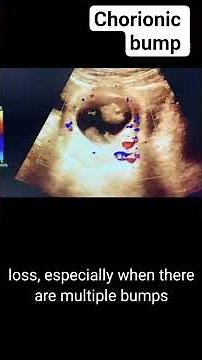

Diagnostic Testing in Pregnancy